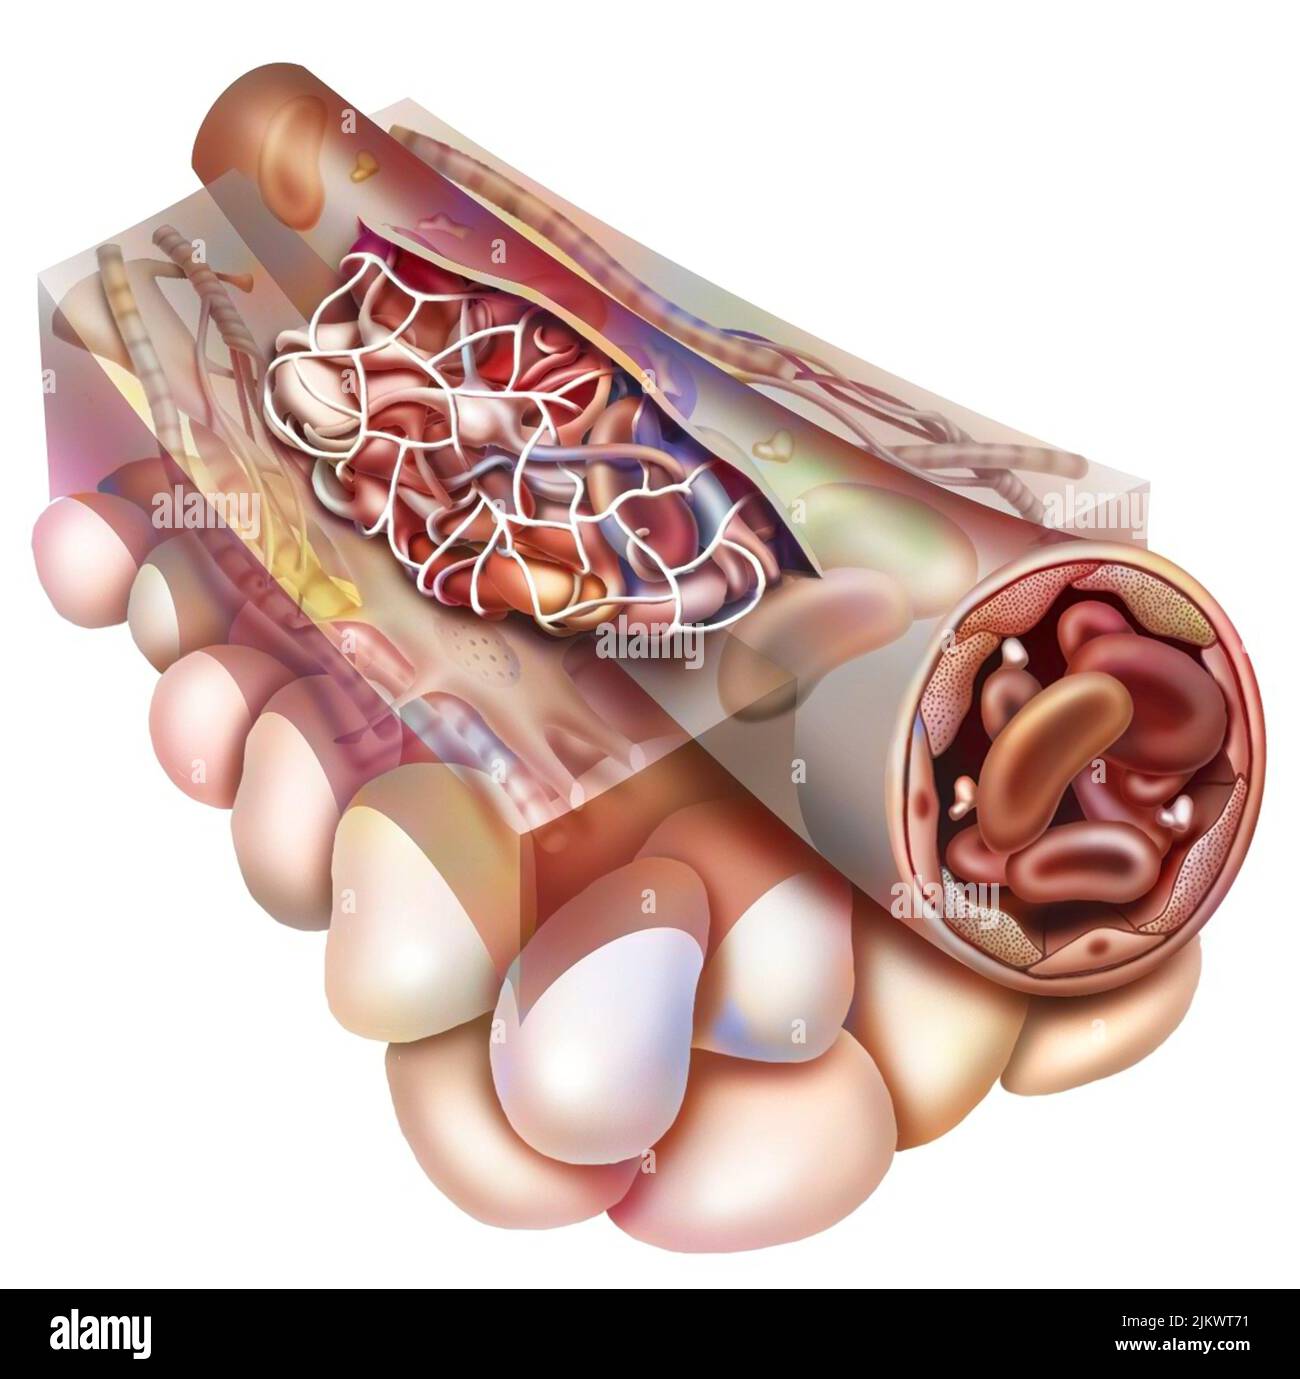

RF2JKWR54–Vaisseau sanguin contenant des globules rouges, des globules blancs, des plaquettes et du plasma.